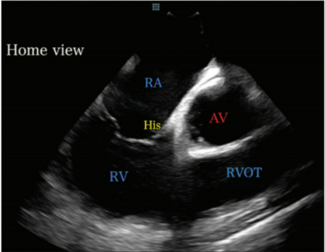

Dr Hany Demo outlines his initial experience with zero-fluoroscopy pulsed field ablation for atrial fibrillation, focusing on patient selection, procedural workflow, and practical tips for incorporating this technique into clinical practice.